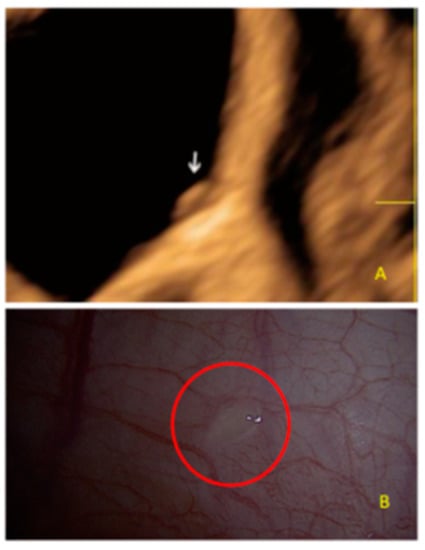

- The presence of velamentous (filmy) adhesions associated to the lesion (we called this a “veil”).

3.2. Cystic Multiple Separate Lesions